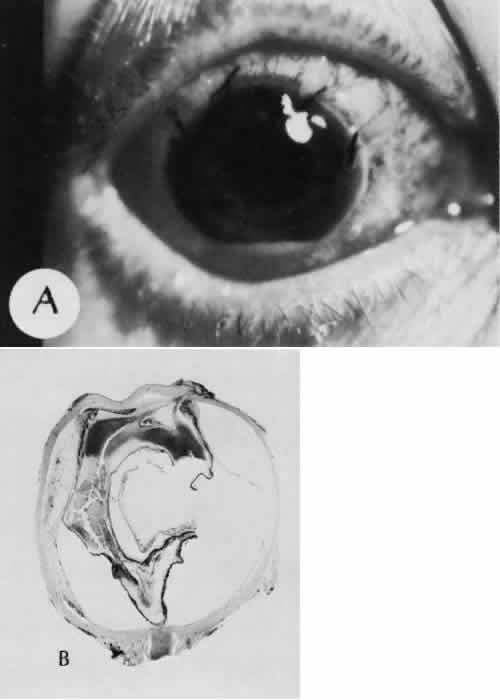

Expulsive choroidal hemorrhage (Fig. 30) is a rare catastrophic complication often resulting in total loss of the eye.93 The site of hemorrhage is probably a sclerotic choroidal arteriole where the vessel crosses the suprachoroidal space from the scleral canal. The sudden hypotension after surgical penetration of the globe causes a bending and then a rupture of the arteriole.94 Although most hemorrhages are massive and immediate, they occasionally are delayed, and some may not occur for days or weeks after surgery. Delayed choroidal hemorrhage may occur at the time of corneoscleral suture removal,95 because of clinically unapparent wound dehiscence or as a result of perforation of a corneal ulcer.

Fig. 30. A case of expulsive choroidal hemorrhage. A. Expulsive choroidal hemorrhage occurred 3 weeks after cataract surgery at the time when a limbal suture was removed. The intraocular pressure was reduced enough to allow shearing forces in the superficial choroid to tear an arteriole resulting in a high-pressure hemorrhage. B. In another case enucleated shortly after cataract extraction because of expulsive hemorrhage, accumulated blood can be identified in the suprachoroidal space. Because of the loose attachment of the choroid to the sclera, all intraocular contents were displaced toward the cataract wound. (Hematoxylin-eosin stain; × 3.)

Histologically, massive choroidal hemorrhagic detachment is associated with a retinal detachment. The retina and choroid may herniate through the scleral wound. A ruptured ciliary artery may be found in the suprachoroidal space.